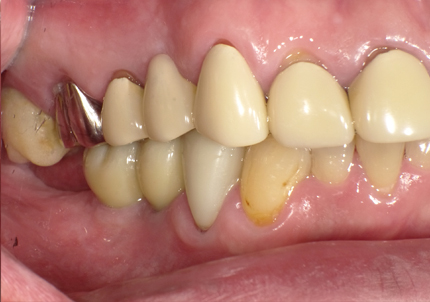

9.左下3本最終補綴装着(2021年11月)

10.口腔内写真(2022年2月)

特に問題無く経過はとても良いです。

患者様ご本人も「良く咬めてとても良い」と満足されています。